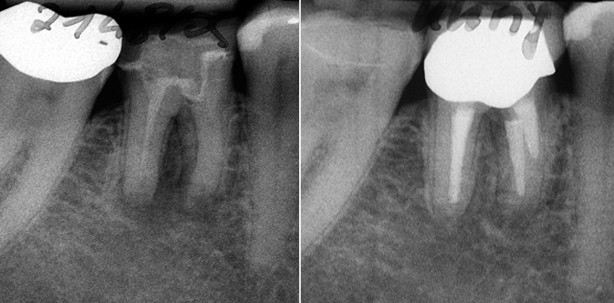

- endometrische (Raypex 4) und röntgenologische Längenbestimmung (Abb. 2)

- Röntgeneinzelbild: Kontrolle der Wurzel kanalfüllungen (Abb. 3)

Die letzte Kontrolle fand knapp zwei Jahre nach Abschluss der endodontischen Behandlung statt. Klinisch zeigten sich gesunde parodontale Verhältnisse, die Sondierungstiefen waren unverändert, der Zahn wies eine physiologische Beweglichkeit auf, es lag keine Furkationsbeteiligung vor. Die Patientin war beschwerdefrei. Röntgenologisch erschienen die periapikalen und interradikulären Läsionen knöchern regeneriert. Ein durchgängig verfolgbarer Desmodontalspalt konnte beobachtet werden (Abb. 4).

Abb. 1: Diese Therapieoption kann Zähne retten, die bereits erfolglos chirurgisch behandelt worden sind und als extraktionswürdig gelten, da durch die Revision die eigentliche Entzündungsursache – die mikrobielle Kontamination des Wurzelkanalsystems – angegangen wird. – Abb. 2: Leider war es nicht gelungen, wie gewünscht einen ausreichend mesioexzentrischenStrahlengang zu erzielen. Da die Silberstifte gerade noch getrennt beurteilbar waren, wurde jedochauf eine erneute Röntgenmessaufnahme verzichtet. Der Kofferdam war zur Erleichterungwährend des Röntgens entfernt und die Zugangskavität speicheldicht verschlossen worden. – Abb. 3: Röntgenkontrollaufnahme nach Füllung der vier Wurzelkanäle und adhäsivemVerschluss mit Komposit. Durch die schräg resezierten Wurzeln erscheinen die Wurzelkanalfüllungen meist zu kurz. – Abb. 4: Röntgenkontrollaufnahme nach etwa zwei Jahren mit stärker exzentrischem Strahlengang (im Vgl. zu Abb. 2 und 3). Hier ist eine bessere Beurteilung der beiden mesialen Wurzelkanalfüllungen möglich. Da der Abstand der distalen Kanäle sehr klein war, ist deren separate Beurteilung weiterhin schwer. Der periapikale und interradikuläre Bereich scheint knöchern ausgeheilt zu sein; ein kontinuierlicher Parodontalspalt ist erkennbar.